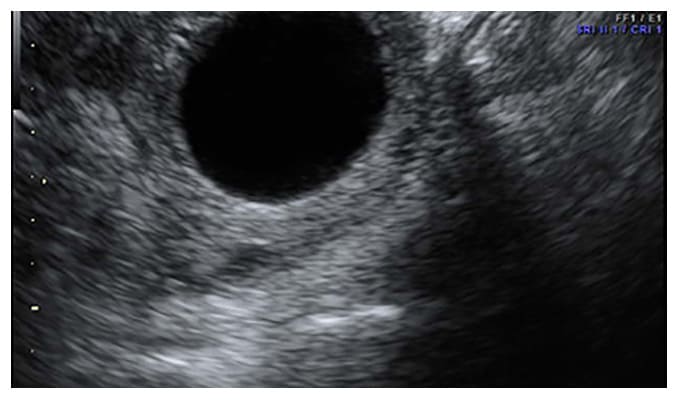

Los quistes de ovario son tumoraciones de contenido líquido, contenido dentro de los ovarios, pueden ser de "agua", "moco" o "sangre" dependiendo del tipo de quiste que se presente y en algunos casos puede ser mixto (contenido líquido y sólido) como los teratomas.

Quistes de Ovario